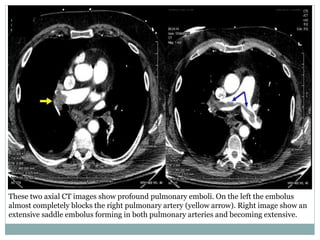

These two axial CT images show profound pulmonary emboli. On the left the embolus

almost completely blocks the right pulmonary artery (yellow arrow). Right image show an

extensive saddle embolus forming in both pulmonary arteries and becoming extensive.